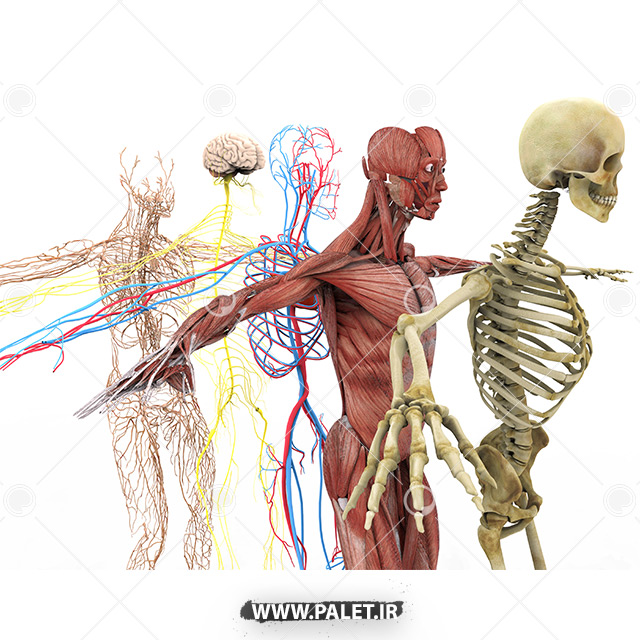

آناتومی سه بعدی بدن انسان عکس گرافی بدن.

اسکلت داربست بدن است تمام قسمت های بدن روی اسکلت قرارگرفته اند بدن انسان از ۲۰۶ قطعه استخوان تشکیل شده است این استخوان ها طوری با نظم کنار هم قرار گرفته اند که انسان را قادر می سازد حرکات دقیقی داشته باشد. استخوان یک نسج بسیار محکم است زیرا در ترکیب آن منرالها مانند کلسیم و دیگر وجود. اسکلت داربست بدن است تمام قسمت های بدن روی اسکلت قرارگرفته اند بدن انسان از ۲۰۶ قطعه استخوان تشکیل شده است این استخوان ها طوری با نظم کنار هم قرار گرفته اند که انسان را قادر می سازد حرکات دقیقی داشته باشد. آناتومی سه بعدی بدن انسان عکس گرافی بدن امعاء و احشاء بدن آناتومی سه بعدی بدن انسان عکس گرافی بدن امعاء و احشاء بدن قلب کبد روده.